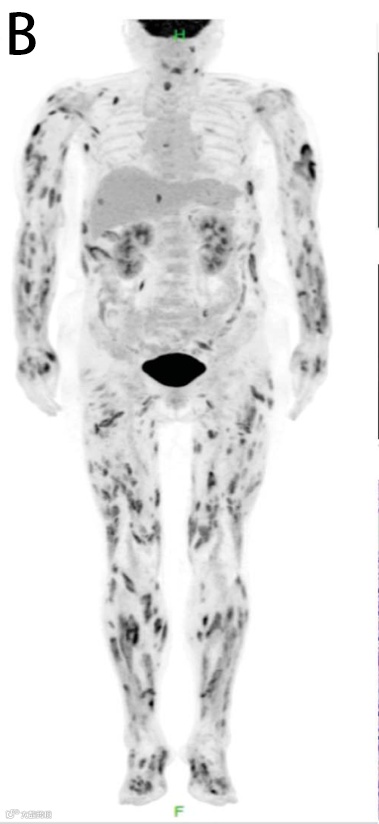

在揭晓谜底之前,我们先来做一个“盲测”。下面有两张经典PET/CT全身MIP 图,请凭借你的直觉,谁是老虎?谁是雪豹?

图B 是“虎纹征” (Tiger Man Sign)

深入虎穴

之所以叫“虎纹”,是因为病灶呈现出“条纹状、线状” (Linear/Stripe-like) 的特征。请仔细看四肢,高代谢灶是顺着肢体长轴分布的,就像老虎身上垂直的斑纹。

“虎纹”是肌肉的纹理。这种征象的核心病理基础是肌肉受累(Muscular involvement)。FDG 沿着肌束(Muscle fascicles) 进行弥漫性或多灶性的浸润。

头号嫌疑人:结节病(Sarcoidosis)。尤其是肌肉结节病(Sarcoid Myopathy)。这是“虎纹征”最经典的对应疾病。约50%-80% 的结节病患者有无症状的肌肉受累,但在PET 上会表现得如此惊心动魄。

其他嫌疑人:皮肌炎(Dermatomyositis)、淋巴瘤肌肉浸润。